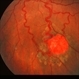

- Condition/keywords

- retinal capillary hemangioma, feeder vessel

- Fundus photo of a retinal capillary hemangioma after treatment of the feeder vessel.